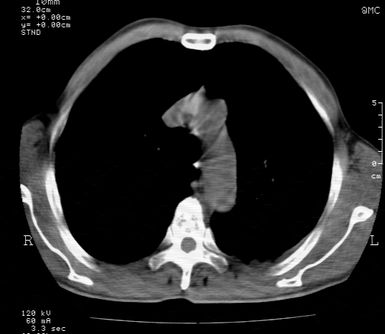

标题: CT24000:M65,胸痛,胸闷月余,既往慢支,肺气肿,肺心病 [打印本页]

标题: CT24000:M65,胸痛,胸闷月余,既往慢支,肺气肿,肺心病

左肺门肿块,相应支气管闭塞,左肺上叶、舌叶大片及散在高密度影,部分呈不张改变,两肺纹粗乱,左侧胸腔积液。考虑左侧中央型肺癌伴阻塞性改变。

左肺门见巨大软组织肿块影,直径约--,境界清,左上肺叶支气管变窄,左上肺舌叶见大片状密实影,余肺纹理增多、紊乱、纤细、部分网格状,两肺透亮度增高,纵隔内见增大多发淋巴结影,心影略左偏,左侧少量胸腔积液。

左侧中央型肺癌伴左上肺舌叶不张、纵隔淋巴结转移,左侧少量胸腔积液。